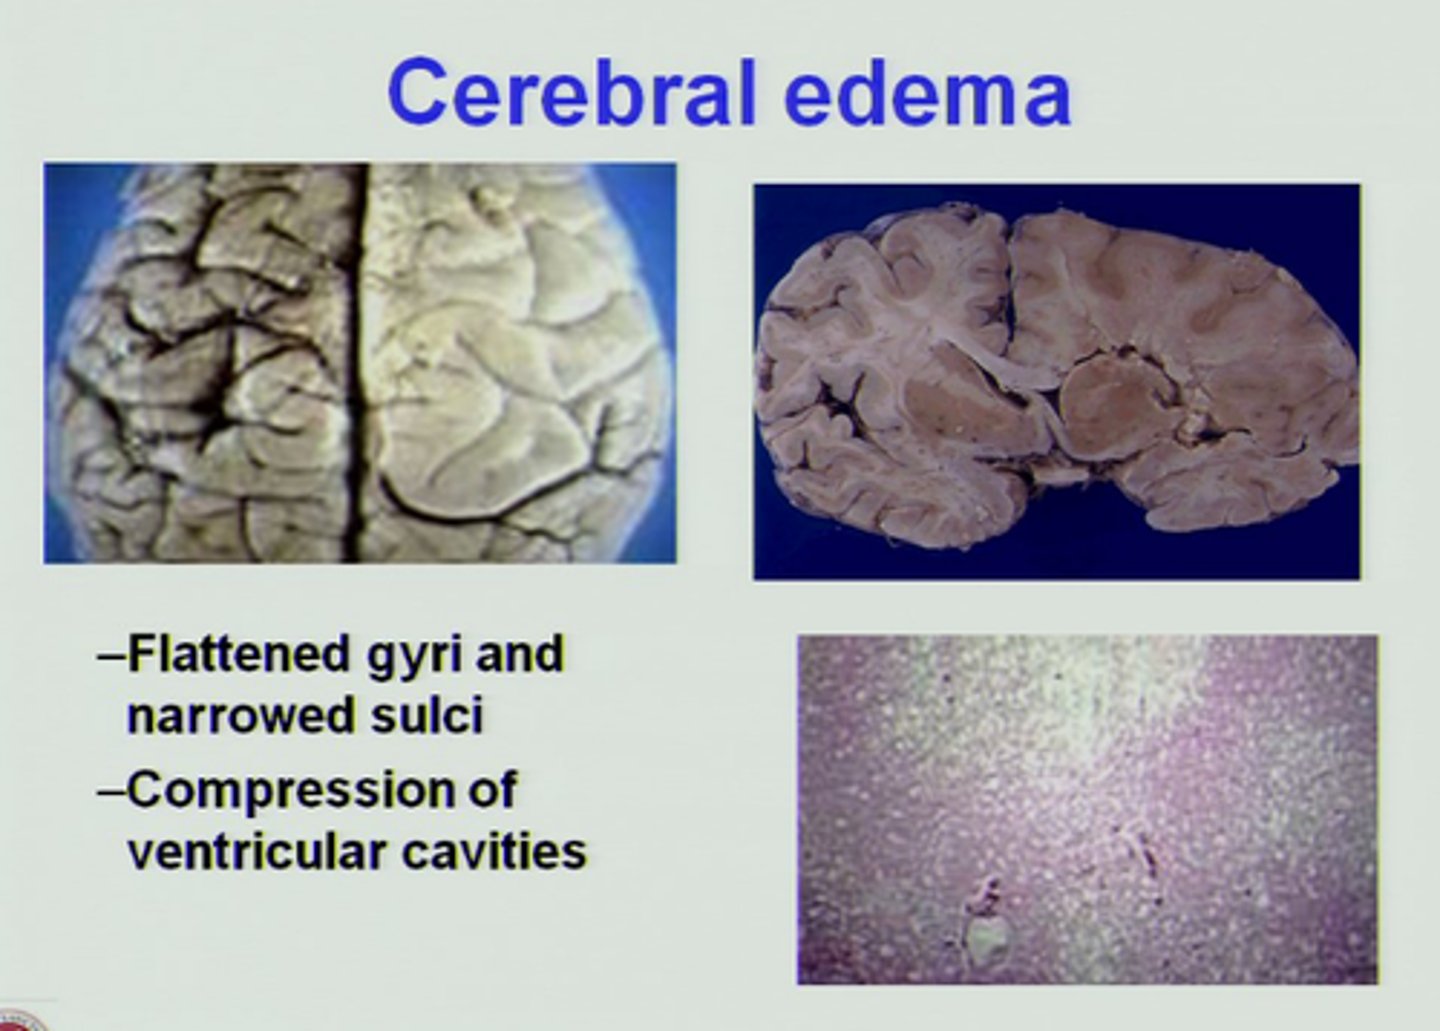

Cerebral Edema

Swelling on the brain